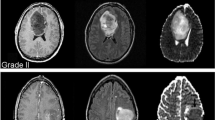

The UBC-OCEAN (Bashashati et al. 2023) dataset is a valuable resource in the field of histopathological research, providing a diverse collection of high-resolution images for two distinct categories of ovarian cancer: whole slide images (WSIs) and tissue microarrays (TMAs). This dataset contains 505 images. The images were resized to 512 × 512 pixels. Details of the dataset are presented in Table 2. Histopathological images of the ovarian subtypes are shown in Fig. 1.